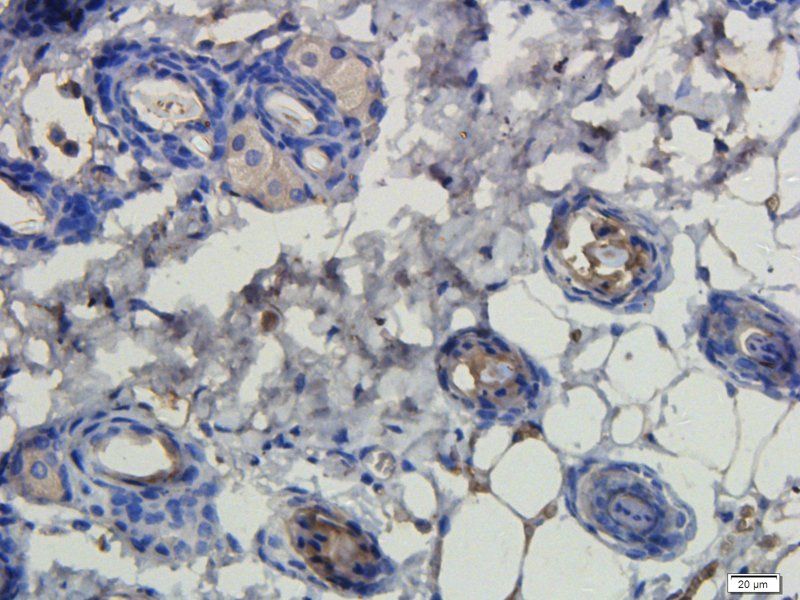

应用稀释比例:IF/ICC: 1:50-400, WB: 1:200-1000, IHC-P: 1:50-400